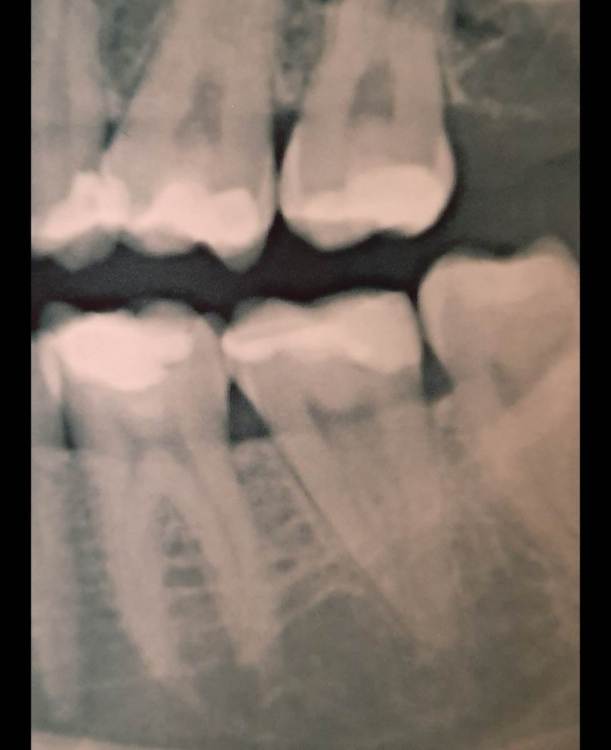

Лана-Лана Опубликовано 6 декабря, 2021 Поделиться Опубликовано 6 декабря, 2021 (изменено) Добрый день. Установили цирконевую коронку на нижнюю семёрку, при примерке я заметила что коронка низкая , но врач убедила что все впорядке типа мой зуб такой и был, самый последний бугор на контакте с восмым зубом с язычной стороны чуть ли не на уровне десны. Теперь когда жуешь и туда попадает что то твердое мясо, яблоко очень больно десну .. я сказала об этом ортопеду но она говорит что по другому не сделать, и предлагает вырвать восьмёрку и засчет этого опустится десна, но это же не выход , да и не хочу я ее удалять, раньше у меня с моим натуральным зубом таких проблем не было.... посмотрите пожалуйста снимки зуба до и фото после, действительно ли у меня был такой низкий зуб? Или это портак? На фото во рту видно что он ниже восьмёрки а край с язычной стороны ещё ниже...и если это плохо сделанно? Можно ли просить переделки ведь он ещё на гарантии? Или это проблемно снять? И что вообще в таких случаях делать если ортопед отказывает в переделке? Писать претензию? Изменено 6 декабря, 2021 пользователем Лана-Лана Ссылка на комментарий